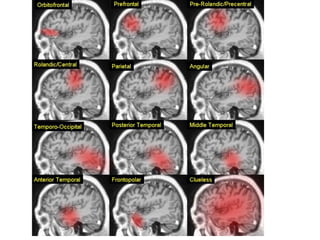

Acute ischemic stroke

 A novel application of MRA is to guide acute stroke

intervention potentially.

 MRA can be a predictor of clinical outcome in acute

ischemic pt. undergoing thrombolysis with IV rtPA in

window period. ( Marks et al 2008).

 The Boston scale ( BASIS) is a classification tool to

help predict outcomes in acute stroke by using MRA

study. ( Torres-Mozqueda et al 2008)

Lt MCA THROMBOSIS